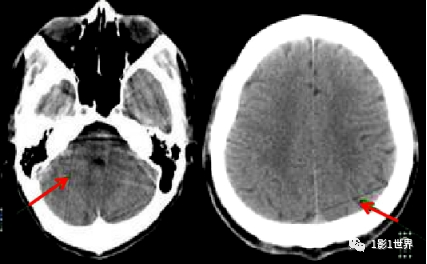

就伪影形成的原因,有设备本身因素,有扫描条件设置因素,有患者因素。正面,展示几种临床上常见的伪影,并分析其形成的原理,克服的办法。规范预热;定期空气校准;维护和保养;检测硬件故障,并更换。也叫条纹状伪影,表现为图像上低密直线,无规律出现。插值算法是导致这类伪影的主要原因。伪影的面积比,要随螺距的增大而增大。致密物体之间的条纹状低密度影;如头部后颅窝亨氏暗区,就是典型的更化束伪影。密度相差较大的物体之间的条带状高低密度影;如胃内气体较多时,肝胃之间的伪影。薄层扫描,厚层重建;改变体位

,避免密度对比过大的物体相接触。部分容积效应,是影像断层扫描中的一个概念,因为层厚的影响,相邻组织间出现重叠,表现出异常影像。